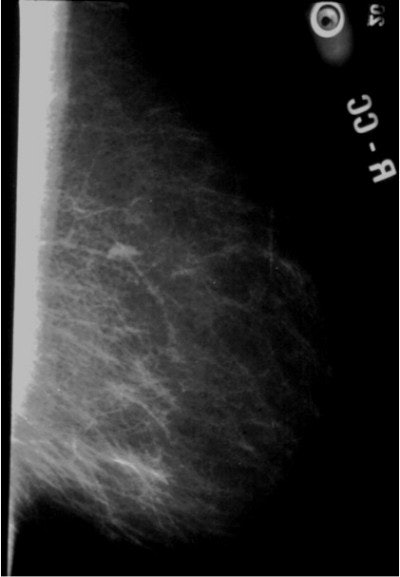

![]() |

| Very dense, glandular pattern seen on mammography in most young women. Breast cancer is extremely hard to find when the breast pattern is this dense, with almost no fatty tissue present. Image courtesy of Dr. Michael Linver. |